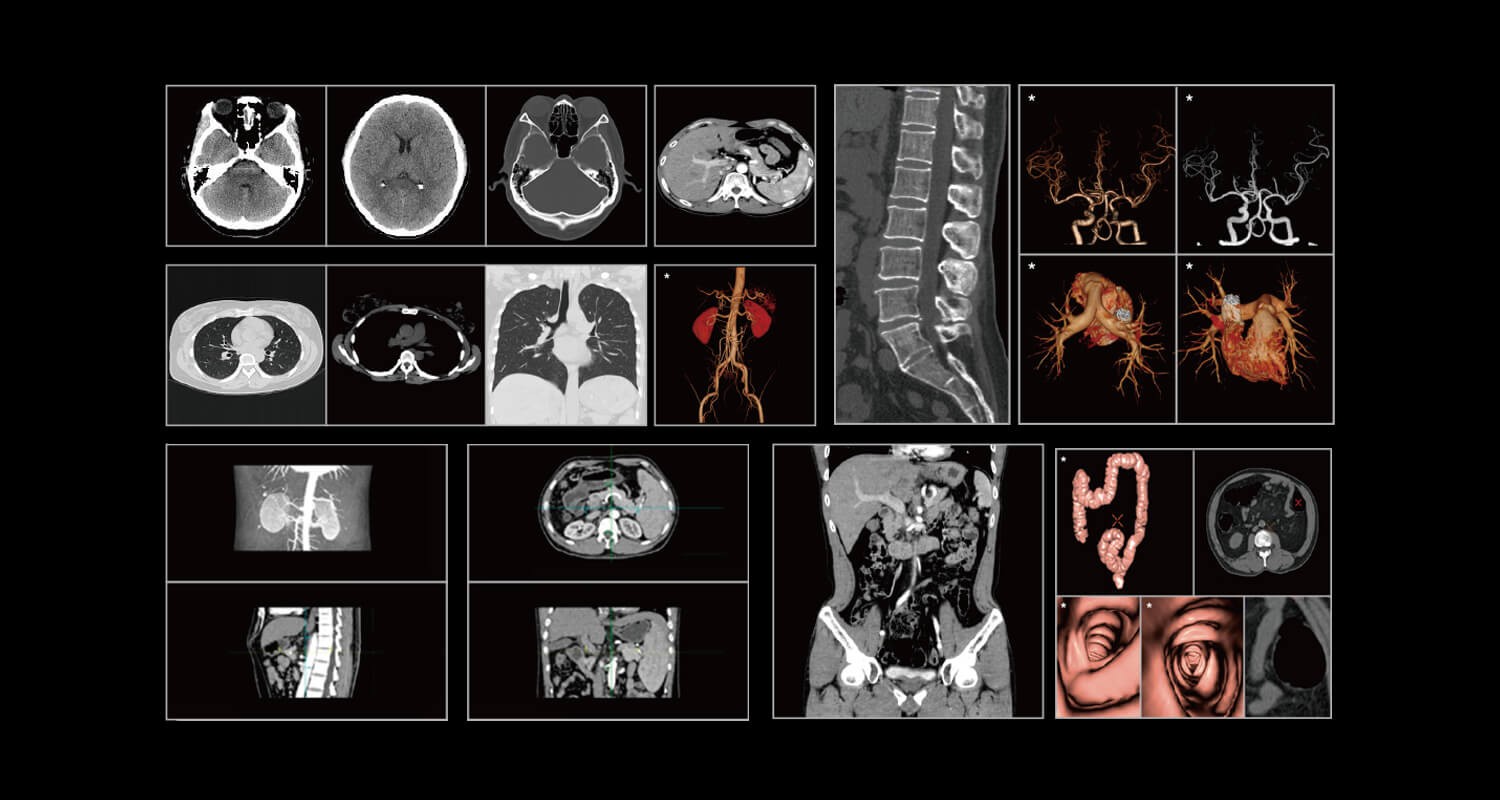

CT

臨床畫廊